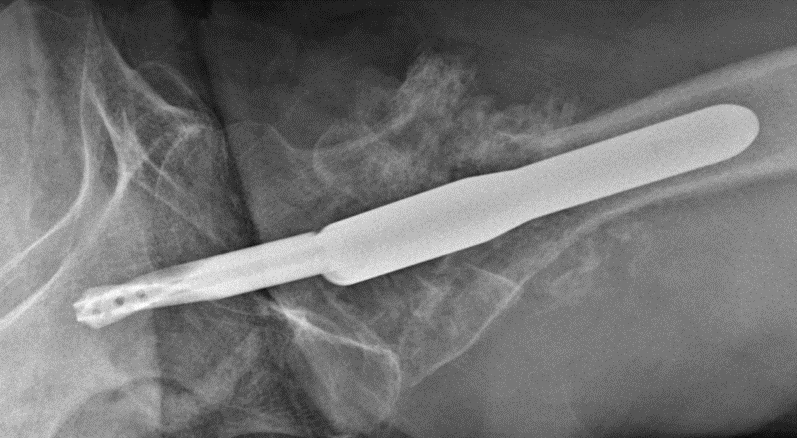

Case: 61 yo F w/ painful right revision TKA after a fall. Elevated serum Co, Cr. Not infected. Treatment of the femur? Management of well-fixed TM tibial cone?

5

Signficant metallosis in the joint and osteolysis about the femoral condyles. Cement-in-cement revision to DFR with retention of well-fixed TM tibial cone. Data on outcomes of retained, well-fixed cones coming in 2023!

2